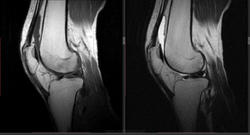

Мужчина 1963 г.р. Жалуется на боль в левом коленном суставе около 6 мес, в последний месяц стало совсем тяжко. Со слов заболел зимой, когда во время прогулки коленки сильно замерзли. Сам думаю на асептический некроз, но смущает множественность поражения.

Дмитрий, я в заболеваниях суставов не дока, но трабекулярный отек вкупе с выпотом может быть обусловлен воспалительными изменениями , но полностью начальные проявления аваскулярного некроза не могу отрицать.

я бы не поставил аваскулярный некроз. если исключена травма, дифференцировать с артритом.

Хрящ не поврежден, для артрита...